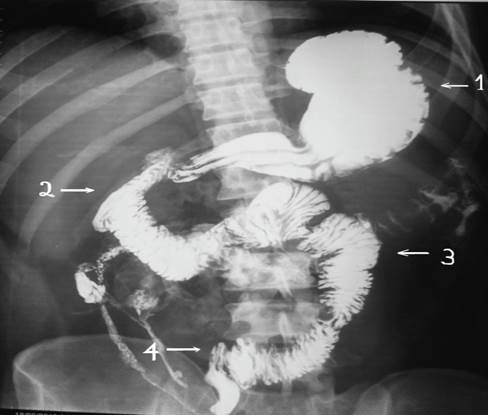

Se verifico el tránsito corto mediante estudio de tránsito baritado intestinal (Imagen 7,8.9)

Ilustración 7 Tránsito gastro-intestinal postquirúrgico; se verifica contraste que pasa desde duodeno al colon directamente

Fuente: Hospital de Especialidades Guayaquil “Doctor Abel Gilbert Pontón”.

Autor: Dr. Fernando Moncayo A.

Ilustración 8 Tránsito gastro-intestinal postquirúrgica, muestra anastomosis yeyuno-colónica.

Ilustración 9 Tránsito gastro-intestinal, muestra anastomosis yeyuno-colónica izquierda baja.